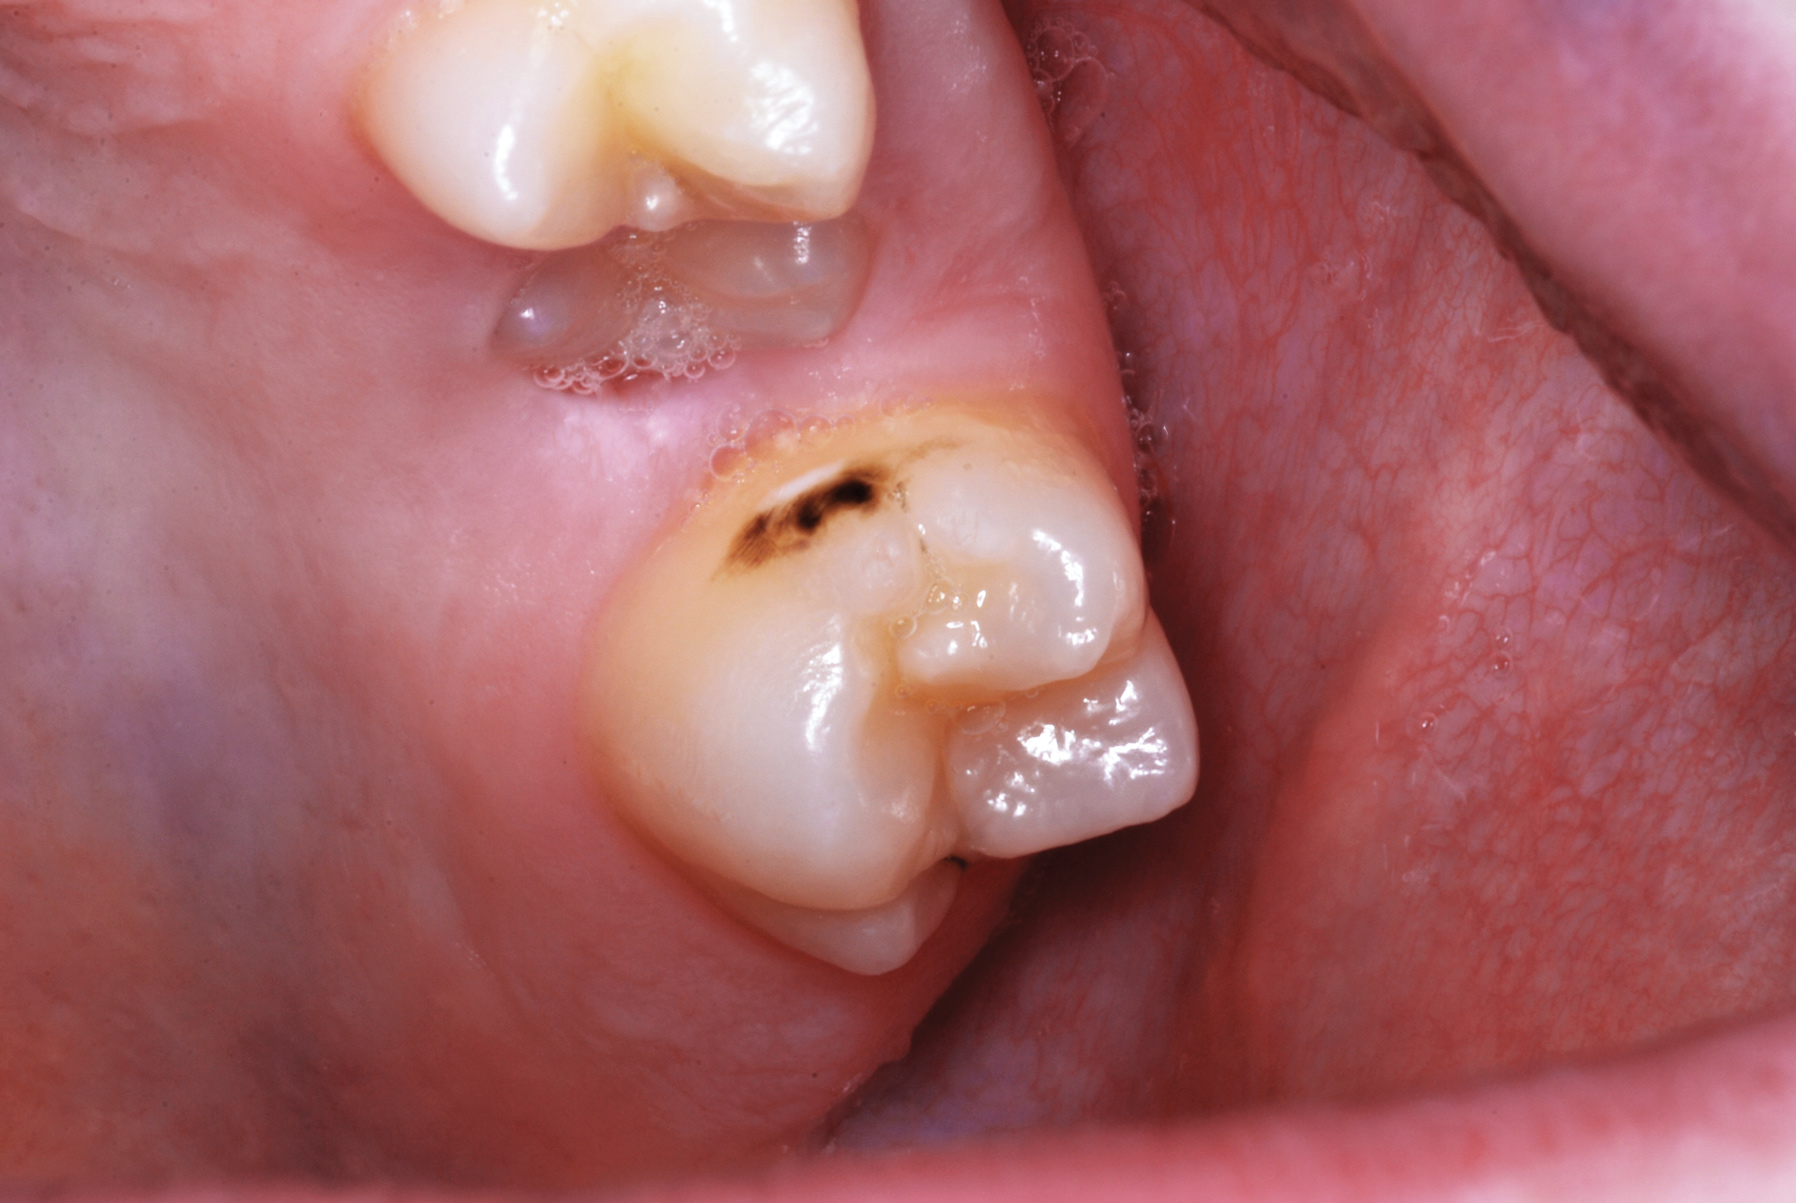

Fig 8. Caries prevention with SDF is critical on distal surfaces of primary second molars to avoid caries infection on mesial surfaces of permanent first molars. Note the Class 2 restorations in both primary molars in this 9-year-old patient whose first molar needed occlusal resin-based composite restoration.

Figure 8